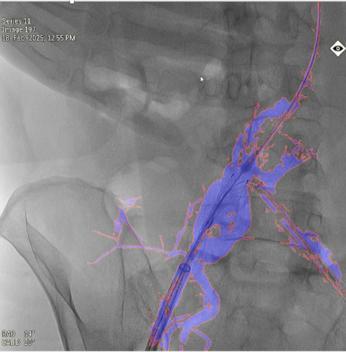

本图研究案例,使用10ml造影剂一次造影,实现EVAR术中髂内动脉重建,图中蓝色部分为造影显示的真实血管,红色边框为图像分割结果,融合图像的透明度可调节,与真实血管完全贴合,血管、器械的细节都清晰可见。